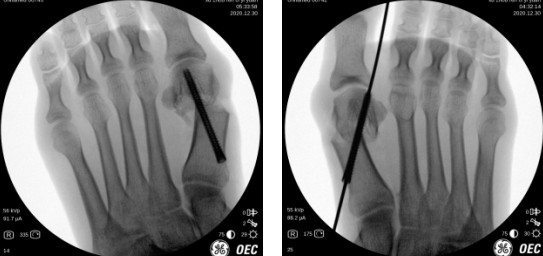

术中透视(左、右足)

第二天,石院长曹主任王岩岩医生团队为患者进行了手术。术中,手术团队切除踇囊,截断第1跖骨头,透视下将跖骨头向外侧足底推移,以克氏针临时固定,再打入螺钉固定,最后透视确认踇外翻角恢复正常,第1跖趾关节半脱位已复位。3个小切口,最大的切口仅0.8cm。